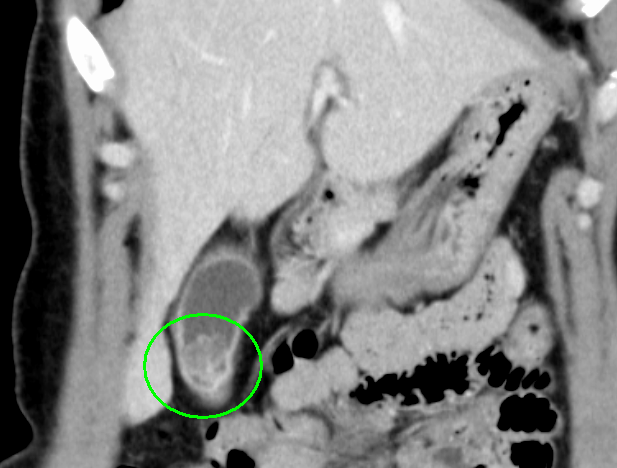

CT画像